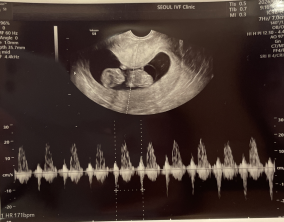

임신 수치 16, 9주차 기적의 기록